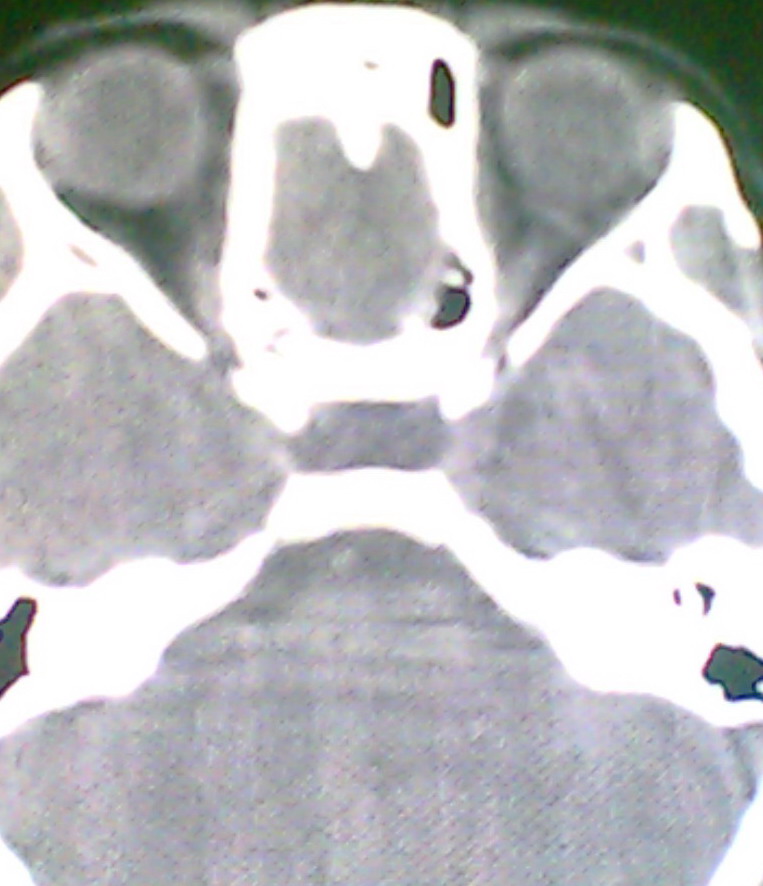

女、18岁,身高1.5左右,鼻塞、流涕数月,两侧瞳孔明显增大,曾与几年前去北京看眼,未发现病变。

考虑起源与蝶窦的粘液囊肿。

支持:考虑起源与蝶窦的粘液囊肿,应该加冠状面扫描

考虑脑膜脑脊液鼻内膨出

考虑起源于蝶窦的粘液囊肿突入鼻咽部。

\"几年前去北京看眼\"不知这句话有何玄机,支持考虑脑膜脑脊液鼻内膨出,膨出口在蝶鞍处

建议冠状面扫描,支持:脑膜鼻内膨出; 蝶窦粘液囊肿突入鼻腔可能性小。

在上级医院冠状位ct扫描后,诊断为:脑膜膨出,已住院准备手术。等待术后结果。